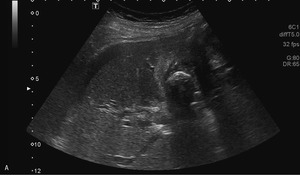

63-letnią kobietę przyjęto na oddział chirurgiczny z przewlekłymi bólami brzucha nasilającymi się w ostatnich 3 tygodniach. Od tygodnia obserwowano zażółcenie powłok, wymioty, odbarwienie stolca i brak łaknienia, co sugerowało żółtaczkę mechaniczną. W ciągu ostatnich 2 miesięcy masa ciała pacjentki zmniejszyła się o 8 kg. Na podstawie wcześniejszych badań USG, wykonanych 10 i 12 lat temu, rozpoznano u niej kamicę pęcherzyka żółciowego. Żółtaczkę potwierdzono w badaniach laboratoryjnych. Wykazano w nich także leukocytozę oraz podwyższone stężenie dimera D i CRP. W wykonanym przy przyjęciu badaniu USG zaobserwowano liczne złogi w pęcherzyku żółciowym i pogrubienie jego ściany z nieregularnym hiperechogenicznym naciekiem w sąsiadującym miąższu wątroby. Stwierdzono także poszerzenie dróg żółciowych wewnątrzwątrobowych w obrębie prawego płata oraz obecność niewielkiej ilości wolnego płynu w jamie otrzewnej (ryc. 1A, B). W dnie pęcherzyka uwidoczniono silne echo zlokalizowane w zarysie ściany narządu (ryc. 1C).

Wszystkie przedstawione warianty rozpoznania są prawdopodobne. Obraz USG z ryciny 1C sugeruje obecność złogu poza obrysem zmienionego zapalnie pęcherzyka żółciowego (rozpoznanie kamicy jest oczywiste na podstawie wcześniejszych obrazów). Bezdyskusyjne jest także rozpoznanie rozległego nacieku, prawdopodobnie zapalnego, w ścianie i w sąsiedztwie pęcherzyka. Fakt ten mocno uprawdopodabnia wytworzenie odleżyny w dnie pęcherzyka, perforacja jego ściany i migracja złogu do jamy otrzewnej.